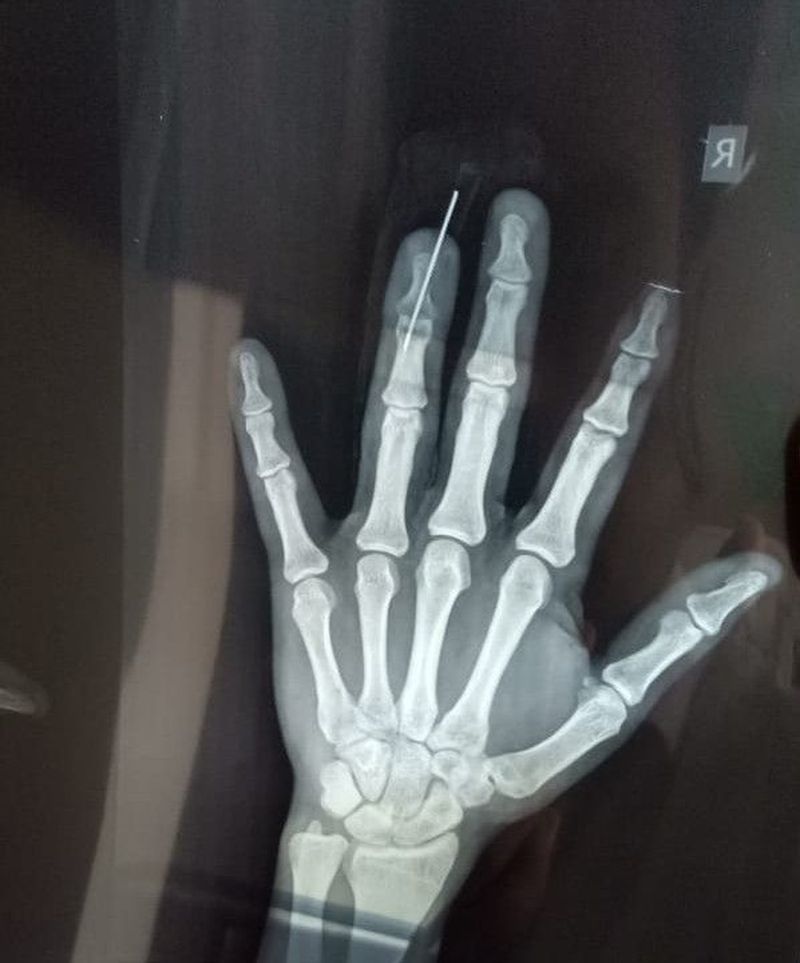

Ring finger fracture

Wire is used to make it straight

Xray

Fracture

Finger